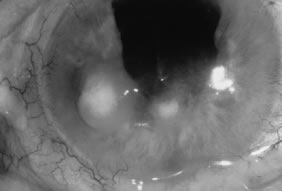

Candida infection typically produces epithelial ulceration, focal necrotizing stromal inflammation, moderate cellular infiltrate and edema in the adjacent stroma, and mild or moderate iritis in the early stages, indistinguishable from bacterial keratitis (Figs. 15, 16, and 17). Fungal elements cannot be detected by biomicroscopy. If untreated, the keratitis evolves to produce dense suppuration and necrosis of the deep stroma. Although multifocal suppuration may develop in polymicrobial keratitis, there is no distinctive sign of mixed Candida and bacterial infection (Fig. 18).

Fig. 15. C. albicans keratitis in an eye following chronic use of corticosteroid drops for herpes simplex keratitis. Note the central suppuration and perforation, endothelial plaques, and hypopyon.

Fig. 16. C. albicans following penetrating keratoplasty in a woman with severe rheumatoid arthritis. Chronic application of corticosteroid eye drop. Note the area of dense, opaque white suppuration that straddles the graft-host junction.